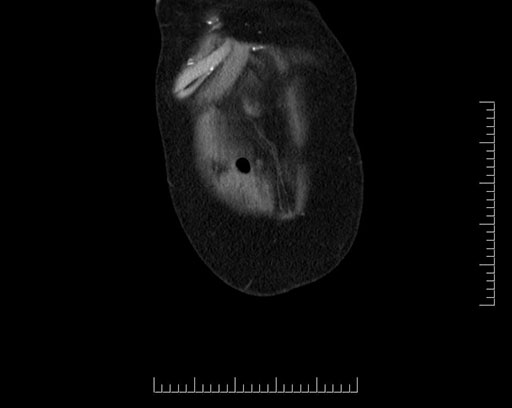

Imaging Analysis

Look through the patient's CT scan to identify any areas of concern for the necessary procedure.

Based on your CT findings, which issue(s) would give reason for "planned slowing down moment(s)" in this case?